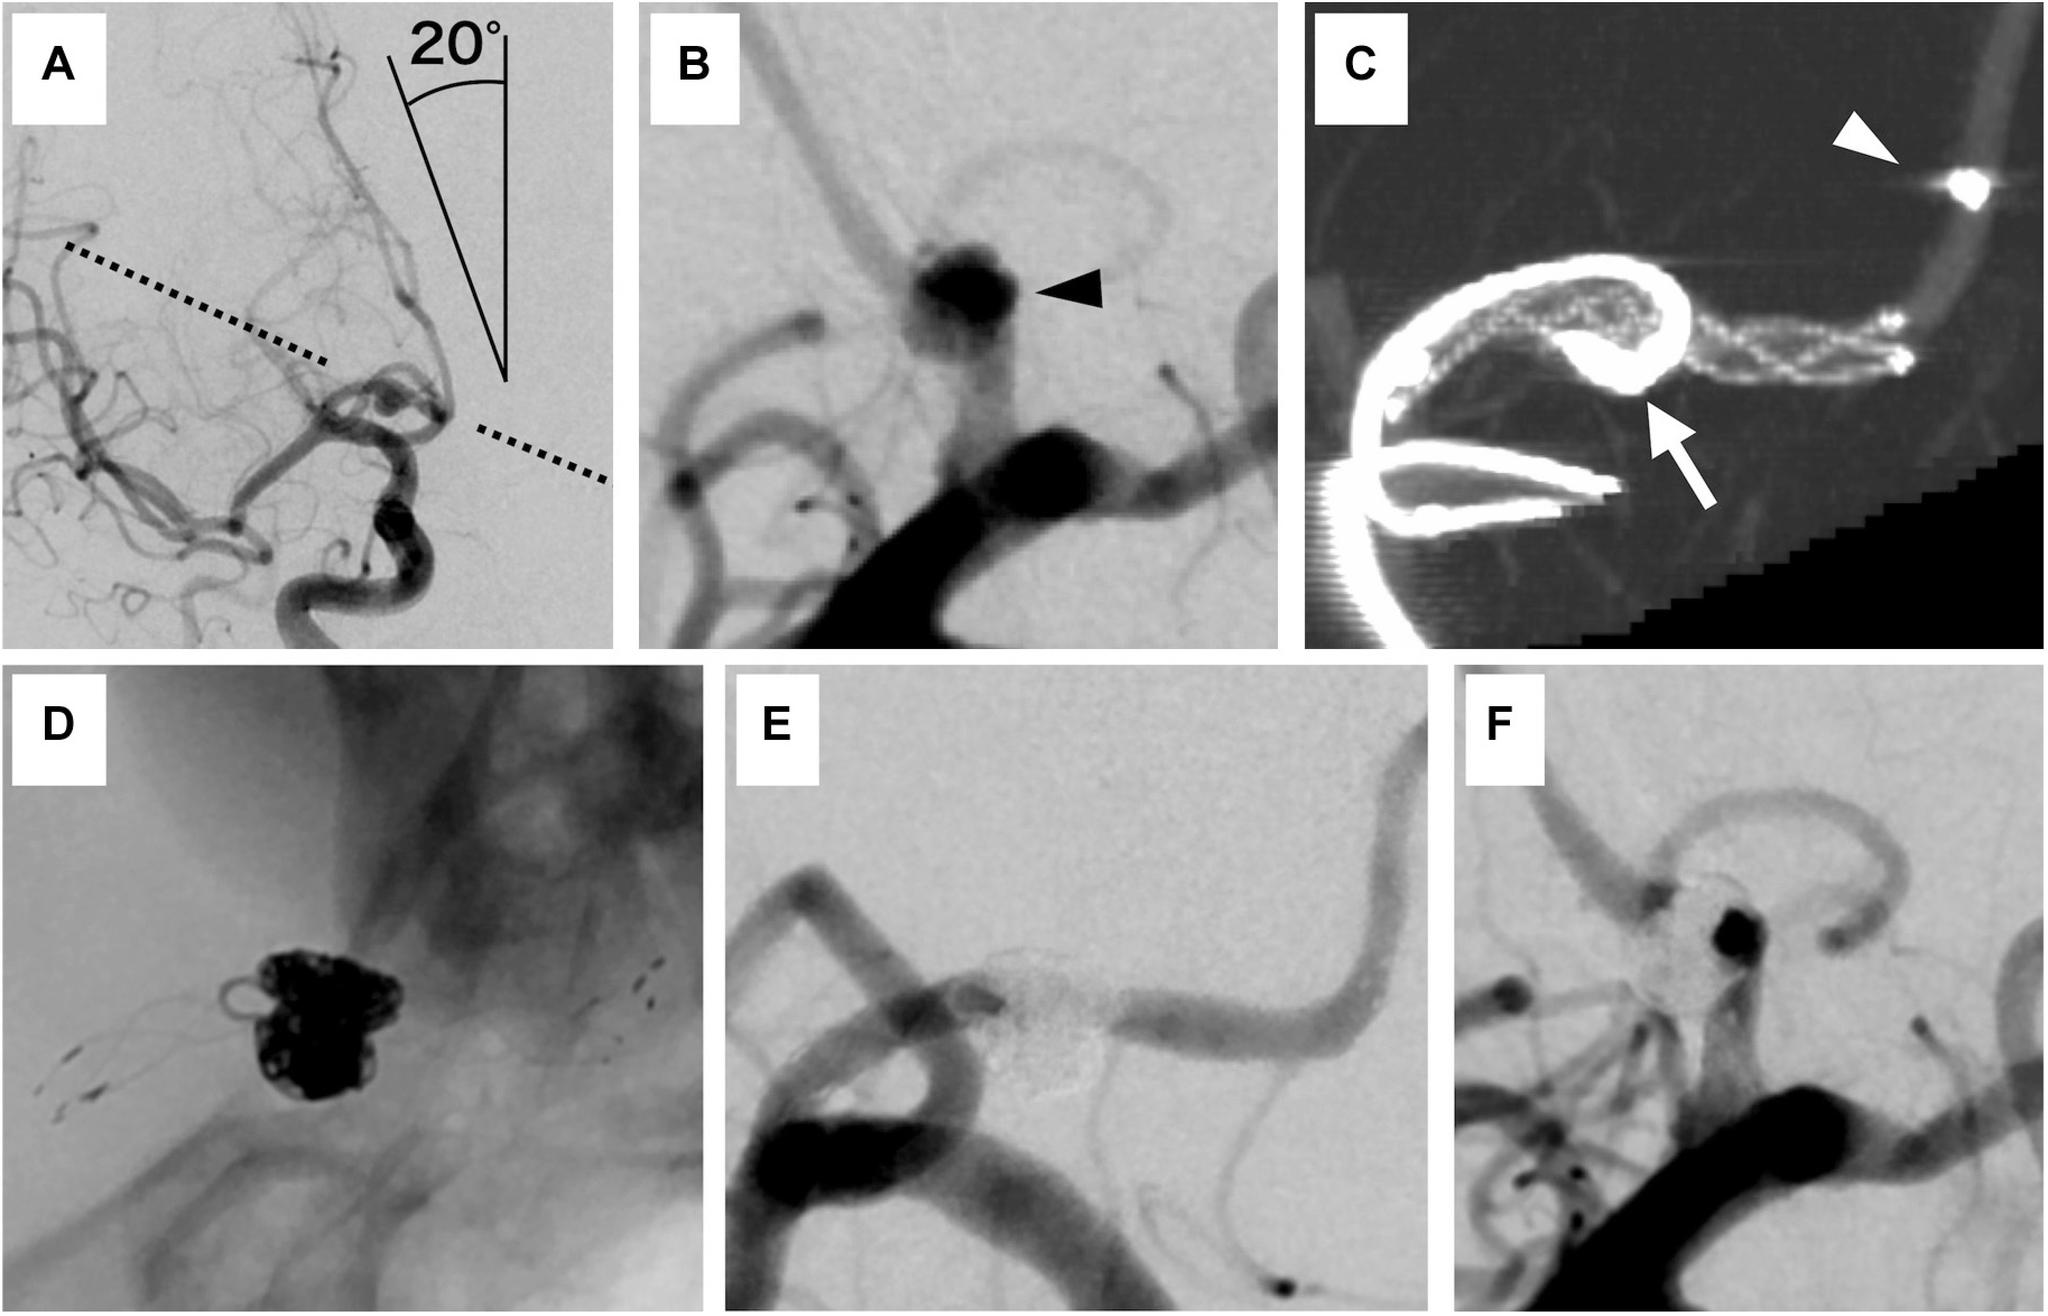

A 51-year-old woman developed subarachnoid hemorrhage the day after transient left hemiparesis. Angiography revealed a ruptured anterior cerebral artery dissecting aneurysm. We conducted stent-assisted coil embolization with the overlapping stent technique on the day after the hemorrhage. She recovered steadily without rebleeding. Six months after embolization, no recurrence was found on angiography.

一名51岁女性在短暂性左侧偏瘫后次日发生蛛网膜下腔出血。血管造影显示大脑前动脉夹层动脉瘤破裂。我们在出血后次日采用重叠支架技术进行了支架辅助弹簧圈栓塞。她恢复平稳,未再出血。栓塞6个月后,血管造影未发现复发。